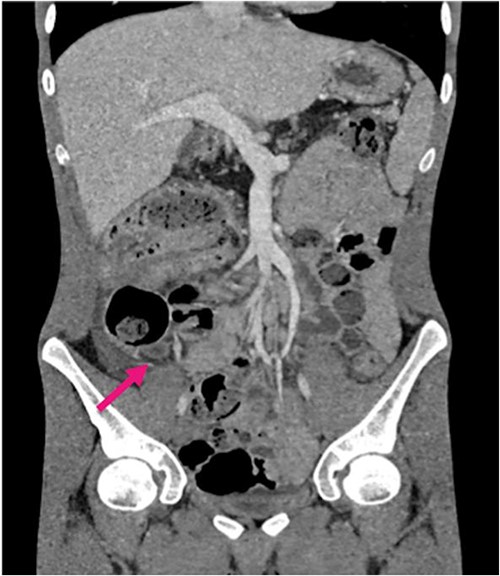

Radiological investigations included a contrast computerized-tomography (CT) of the abdomen/pelvis and suggestive of intussusception of the caecum into the ascending colon, with a thickened appendix. Due to the presence of faecal loading, it was not clear radiologically whether the combined clinical picture was suggestive of distal intestinal syndrome (Figs 1 and 2) due to faecal loading only, or true intussusception of the appendix.

Contrast CT axial sections showing the enhanced thickened appendix (white) intussuscepts with fat stranding, into the ascending colon. Distal faecal loading also observed.